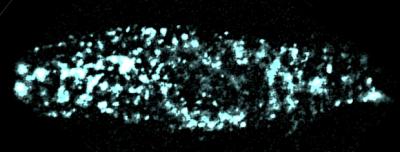

Goldstein's team observed E1 in live, mammalian cells at remarkable sensitivity, counting the proteins in individual channels, something that had never been done before in this area of research. Because this mechanism has been so widely debated, Goldstein and his team used three different means to count E1 — including tagging them with different fluorescent colors and using a scorpion toxin to bind to Q1. Each time, the team got the same results.